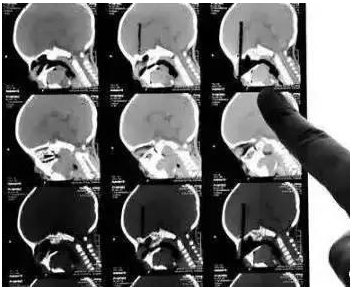

C T

The inspection principle of CT is that X-ray will slice through the human body and post-process it into secondary imaging through computer calculation.

Advantages: It can be seen from the fault, and more information can be displayed after post-processing.

Disadvantages: The cost is more expensive than X-ray photography, and the radiation dose of CT examination is usually higher than that of single X-ray photography.

CT 3D reconstruction of chopsticks inserted into the eyeball)